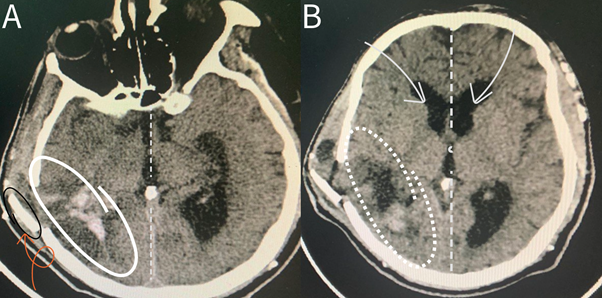

A 55-year-old male, diagnosed with end-stage renal disease (ESRD) and hypertension, was urgently transported to the emergency department due to the sudden onset of a severe headache. This incapacitating headache, which occurred in a relaxed, non-strenuous setting, was accompanied by recurrent episodes of vomiting and rapidly progressed to a state of confusion. Additionally, the patient reported experiencing eye pain and blurred vision immediately following the onset of this distressing episode. This intricate clinical presentation is compounded by the patient's extensive medical history, including a 15-year battle with diabetes mellitus (DM), further complicated by diabetic nephropathy and retinopathy over the past 5 years. Moreover, the patient has been managing hypertension for 6 years, necessitating ongoing antihypertensive medications. 5 years ago, the diagnosis of end-stage renal disease was established, leading to the initiation of a maintained hemodialysis regimen. Upon arrival, the patient exhibited generally stable vital signs, except for a notable blood pressure reading of 210/100 mm Hg. Although the Glasgow Coma Scale (GCS) indicated a score of 14 out of 15, suggestive of relatively preserved consciousness, the patient was notably unable to articulate speech. This condition further deteriorated to a GCS score of four out of 15, necessitating immediate surgical intervention. During the chest examination, bilateral decreased air entry was evident, with a more pronounced reduction noted on the left side. On further neurological assessment, the patient presented with a striking clinical finding: left-sided paraplegia, indicating impaired motor function in the lower limbs. A non-contrast brain CT scan revealed a hyperdense lesion on the right side of the brain, consistent with intraparenchymal hemorrhage (Figure 1). This hemorrhagic region was accompanied by a significant midline shift measuring approximately 9 millimeters, indicative of the displacement of brain structures toward the opposite side due to the intracranial hemorrhage.

Figure 1 Non-contrast preoperative brain CT scan depicting right intraparenchymal hemorrhage and evident midline shift.(A-C): different levels of brain CT scam showing the size and extent of the ICH.